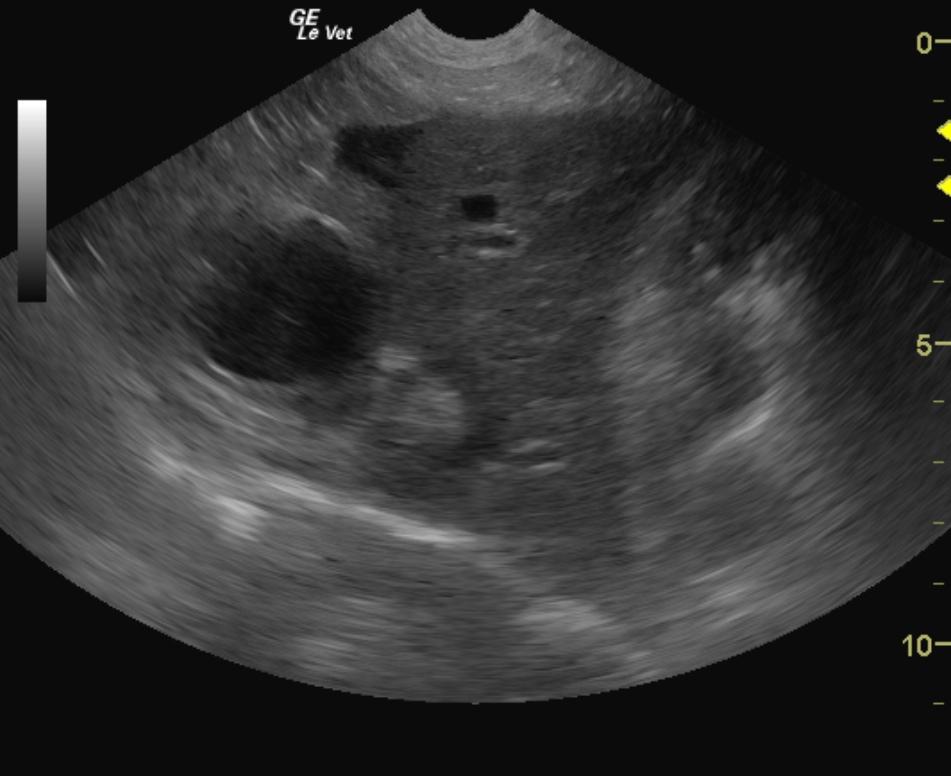

Chronic active hepatitis, cholangiohepatitis presentation with portal hypertension. Suspect infectious disease such as Leptospirosis or hepatotoxin. Ascites likely owing to portal hypertension. Chronic interstitial renal pattern. Ascites.

The abdomen in this patient presented excessively small liver with increased portal markings and coarse parenchyma with irregular capsular changes consistent with chronic hepatic fibrosis, cholangiohepatitis and portal hypertension given the ascites present. The gallbladder was thickened and mildly distended. The hepatic veins were excessively dilated due to over circulation and aggressive fluid therapy, therefore biopsies were not performed. 12-14 hours of diminishing fluid rate should provide for a safer window for ultrasound guided biopsy to assess parenchymal changes and rule out underlying lymphoma or other neoplastic event as well as assess for other source of cholangiohepatitis such as copper storage disease. Some ascites was noted around the upper gastrointestinal tract adjacent to the liver lobe. The omentum was mildly echogenic due to emerging ascites. The kidneys presented subcapsular fluid accumulation with diffuse interstitial pattern. Chronic leptospirosis can also present in this manner.